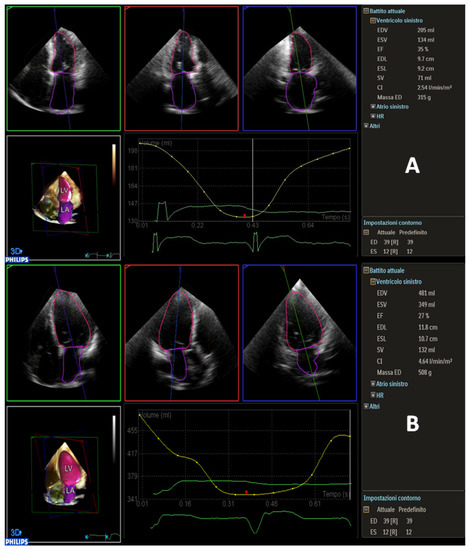

| LVEF, % | 29 ± 8 | 32 ± 7 | 26 ± 5 | 0.003 |

| LVEDV, mL | 181 ± 49 | 135 ± 38 | 228 ± 48 | <0.001 |

| LVEDV/I, mL/m2 | 103 ± 28 | 80 ± 20 | 126 ± 27 | <0.001 |

| LVESV, mL | 127 ± 42 | 88 ± 40 | 167 ± 41 | <0.001 |

| LVESV/I, mL/m2 | 77 ± 24 | 60 ± 20 | 94 ± 23 | <0.001 |

| LV mass, gr | 275 ± 70 | 249 ± 63 | 301 ± 69 | 0.035 |

| LVEF, % | 0.981 (0.92–0.996), p < 0.001 | 0.938 (0.75–0.986), p < 0.001 |

| LVEDV/i, mL/m2 | 0.996 (0.985–0.999), p < 0.001 | 0.994 (0.736–0.999), p < 0.001 |

| LVESV/i, mL/m2 | 0.998 (0.992–0.999), p < 0.001 | 0.997 (0.986–0.999), p < 0.001 |